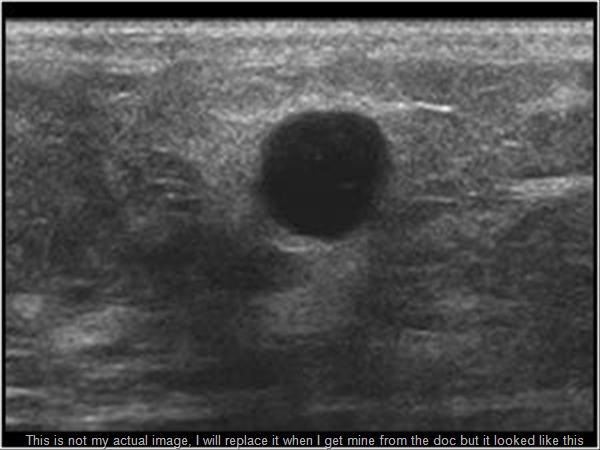

I climb on the table and wait. She pulls out the ultrasound wand thing and, “Whew that’s chilly!… yep, I remember that cold slime used for this machine. She asks me where I felt the lumps (of course I couldn’t find them now) but she ran the wand over the area. It wasn’t too long before I realized I would MUCH rather have the mammo than this. I swear she was trying to press the wand all the way through my chest cavity to see the other side!! I told her baby ultrasounds are MUCH more fun! She laughs and pushes harder! Ugh, this went on like this forever while I watched the little screen show my ta-ta tissue and, wait… why are you focusing on that spot… what is that … why are you measuring??? …mommy?

I keep my cool, I only let a few tears slip, mostly unnoticed, out my eye. I was afraid and of course, she would not tell me anything. After it was over she left to get let the radiologist see her findings. I was really wishing my hubby was in here with me now. I wasn’t sure if the radiologist would come in this room where I waited in my smock feeling vulnerable or if I would have a chance to get dressed, get my hubby, and sit in an office. Nope. In comes nurse lady and radiologist man…. he informs me that they didn’t find anything where I felt something, and that where it was painful under my armpit was a very normal looking lymph node, BUT… (why is there always a BUT…) but the mammogram did find three cysts and the ultrasound confirmed. One was a “simple cyst,” it is to be documented and nothing else really has to be worried about it, however… (of course there is a however…. ) … however the other two cysts are what they call “complex cysts.” These are ones that have a chance to turn into something more, we will have to watch them…blah blah.. come back in six months… blah blah… I kind of couldn’t focus anymore at that point. I caught that he said a complex cyst could turn into a simple cyst or they could turn into… blah blah…. Stress induced ADD was in full force, but that is ok, I will just research it when I get home… (thoughts) no offense fella but really I don’t want to hear anything else right now… Bec, remember the words he used… simple and complex cysts…. ok… now be polite and thank him, good…. and breathe.